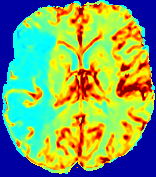

LesionRefer to captionRefer to captionRefer to captionRefer to captionRefer to captionRefer to caption𝐕rgbsubscript𝐕𝑟𝑔𝑏{\bf{V}}_{rgb}Refer to captionRefer to captionRefer to captionRefer to captionRefer to captionRefer to caption𝐕2subscriptnorm𝐕2{\|\bf{V}}\|_{2}Refer to captionRefer to captionRefer to captionRefer to captionRefer to captionRefer to captionRefer to caption3.53.53.52.82.82.82.12.12.11.41.41.40.70.70.70.00.00.0(mm/s)𝑚𝑚𝑠(mm/s)D𝐷DRefer to captionRefer to captionRefer to captionRefer to captionRefer to captionRefer to captionRefer to caption0.0200.0200.0200.0160.0160.0160.0120.0120.0120.0080.0080.0080.0040.0040.0040.0000.0000.000(mm2/s)𝑚superscript𝑚2𝑠(mm^{2}/s)Slice #1Slice #2Slice #3Slice #4Slice #5Slice #6

Figure 4: PIANO feature maps for another patient in the ISLES 2017 training set, where the lesion is located in the right hemisphere. Top row: segmented stroke lesion region (white) on different slices. The corresponding slices for the PIANO feature maps are shown in the following rows.

For a better insight into an estimated velocity field 𝐕𝐕{\bf{V}} and diffusion field 𝐃𝐃{\bf{D}}, we compute the following maps: (1) 𝐕rgbsubscript𝐕𝑟𝑔𝑏{\bf{V}}_{rgb}: Color-coded orientation map of 𝐕=(Vx,Vy,Vz)T𝐕superscriptsuperscript𝑉𝑥superscript𝑉𝑦superscript𝑉𝑧𝑇{\bf{V}}=(V^{x},V^{y},V^{z})^{T}, obtained by normalizing 𝐕𝐕{\bf{V}} to unit length and mapping its 3 components to red, green, blue respectively; (2) 𝐕2subscriptnorm𝐕2\|{\bf{V}}\|_{2}: 222 norm of 𝐕𝐕{\bf{V}}; (3) D𝐷D: scalar field in Eq. 5.

Fig. 3 and Fig. 4 show the PIANO feature maps estimated from two ISLES 2017 patients: all are highly consistent with the lesion in both cases. Details of the blood flow trajectories are revealed in 𝐕rgbsubscript𝐕𝑟𝑔𝑏{\bf{V}}_{rgb} by the ridged patterns and the sharp changes of colors in the unaffected (right) hemisphere, while the flat patterns appearing within the lesion provide little directional information about the velocity and indicate low velocity magnitudes. Velocity magnitudes are more directly visualized via 𝐕2subscriptnorm𝐕2\|{\bf{V}}\|_{2}, from which one can easily locate the lesion where 𝐕2subscriptnorm𝐕2\|{\bf{V}}\|_{2} is low. D𝐷D also indicates lower diffusion values in the lesion, though with less contrast potentially due to the fact that it captures the accumulated effect of CA diffusion at the voxel-level.